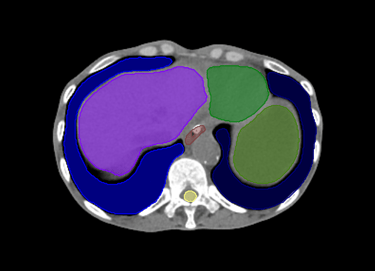

O SegmentaR foca na segmentação automática das três regiões fundamentais para o planejamento de radioterapia: cabeça e pescoço, tórax e pelve. Essas são as regiões essenciais que todo profissional precisa para uma segmentação precisa e eficiente.

Tórax

Coração

Duodeno

Esôfago

Estômago

Fígado

Laringe

Medula Espinhal

Pulmão Direito

Pulmão Esquerdo

Rim Direito

Rim Esquerdo

Glândula Tireoide

Traqueia

Mama Direita

Mama Esquerda